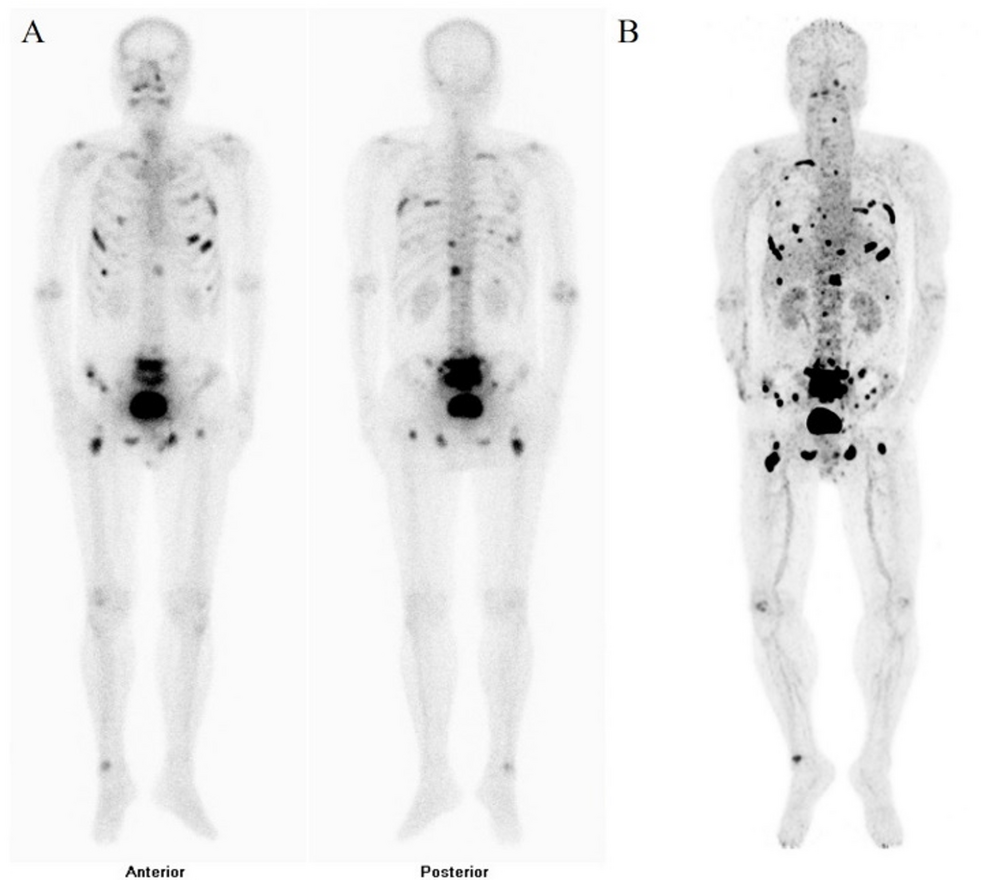

Fig. 2

A direct comparison of 99mTc-MDP bone scintigraphy and 68Ga-DOTA-IBA PET/CT images in a prostate cancer patient was conducted over a one-week interval. An 80-year-old man with metastatic prostate cancer. 68Ga-DOTA-IBA PET/CT (B) demonstrated a higher number of bone metastatic lesions when compared with a 99mTc-MDP bone scan (A) and presented them with greater clarity.